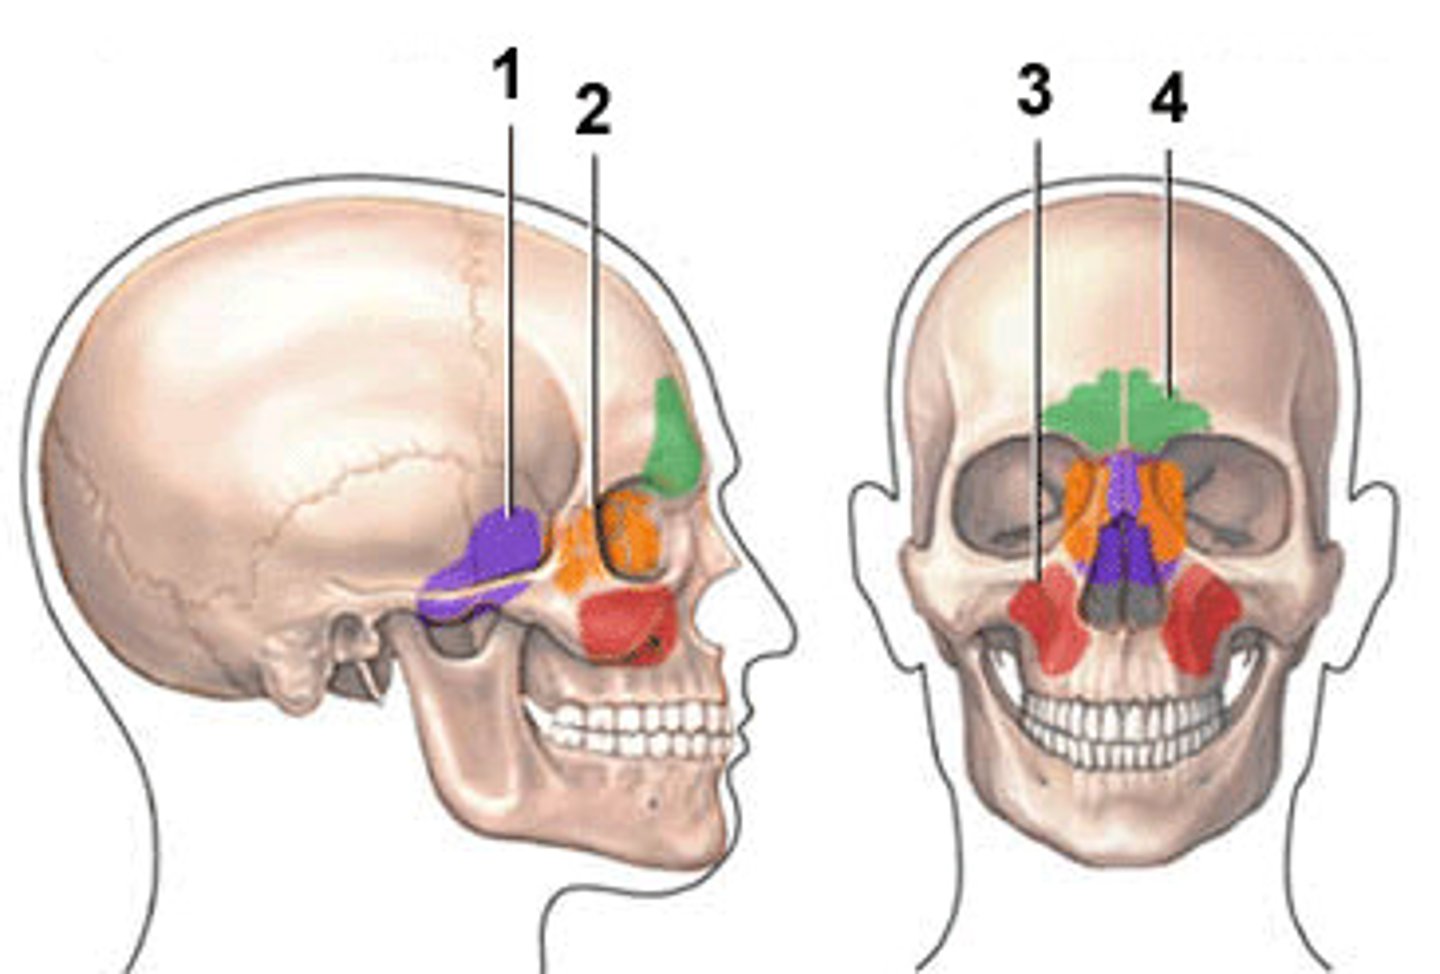

coronal suture

sagittal suture

squamosal suture

lambdoidal suture

Ethmoid bone

parietal bone

sphenoid bone

occipital bone

temporal bone

frontal sinuses

What is 4?